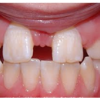

Diasteem

Diasteem – vahe esimeste hammaste vahel. Esineb 50%-l 6-8 aastastel lastel. Kuni 2 mm diasteemi puhul on, peale lateraalse intsisiivi ja silmahamba lõikumist, võimalik diasteemi iseeneslik sulgumine. Diasteem, mille suurus...